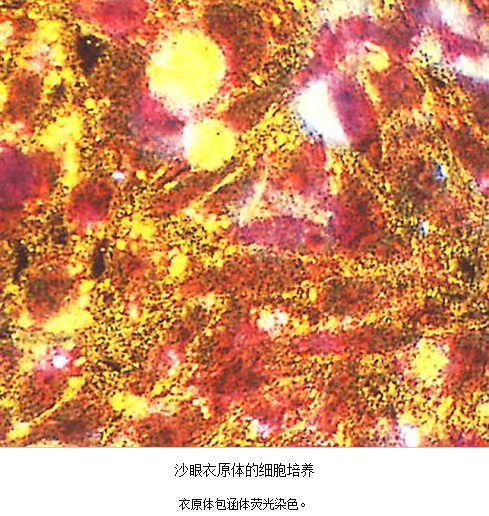

急性子宫颈炎的病原体:①性传播疾病病原体:淋病奈瑟菌及沙眼衣原体,主要见于性传播疾病的高危人群;②内源性病原体:部分子宫颈炎的病原体与细菌性阴道病病原体、生殖支原体感染有关。但也有部分患者的病原体不清楚。沙眼衣原体及淋病奈瑟菌均感染子宫颈管柱状上皮,沿黏膜面扩散引起浅层感染,病变以子宫颈管明显。除子宫颈管柱状上皮外,淋病奈瑟菌还常侵袭尿道移行上皮、尿道旁腺及前庭大腺。

3.病原体检测 应作衣原体及淋病奈瑟菌的检测,以及有无细菌性阴道病及滴虫阴道炎。检测淋病奈瑟菌常用的方法有:①分泌物涂片革兰染色,查找中性粒细胞内有无革兰阴性双球菌,由于子宫颈分泌物的敏感性、特异性差,不推荐用于女性淋病的诊断方法。②淋病奈瑟菌培养,为诊断淋病的金标准方法。③核酸检测,包括核酸杂交及核酸扩增,尤其核酸扩增方法诊断淋病奈瑟菌感染的敏感性及特异性高。检测沙眼衣原体常用的方法有:①衣原体培养,因其方法复杂,临床少用。②酶联免疫吸附试验检测沙眼衣原体抗原,为临床常用的方法。③核酸检测,包括核酸杂交及核酸扩增,尤以后者为检测衣原体感染敏感、特异的方法。但应做好质量控制,避免污染。